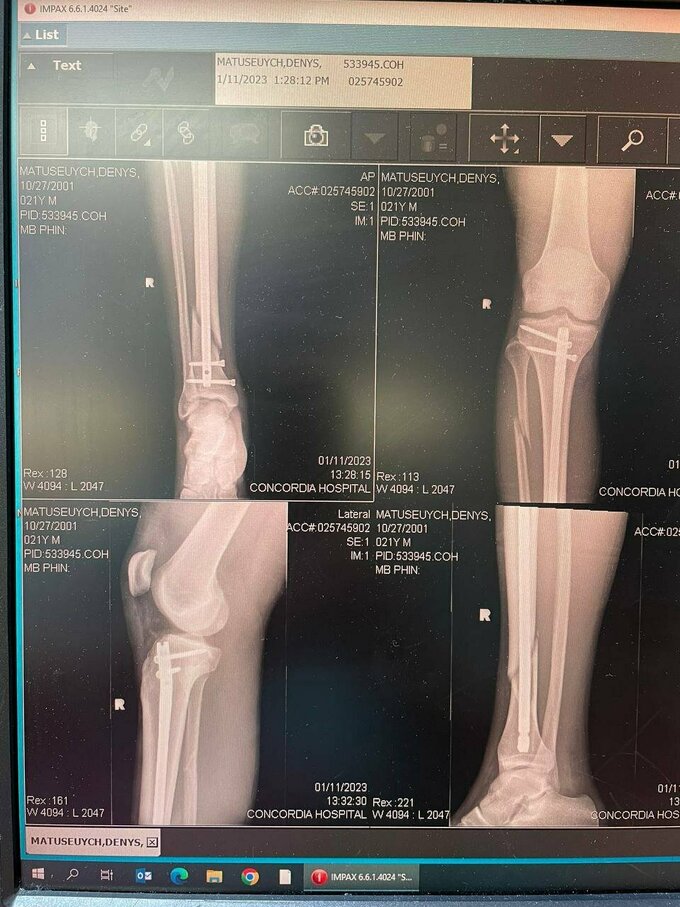

ФОТО. Вставили 4 болта. Матусевич получил перелом и перенес операцию

Вставили 4 болта: два под коленом, два над голеностопом и спицу посередине кости. Полное восстановление – до года, а на лед можно пробовать выходить, когда срастется кость – 3–4,5 месяца.